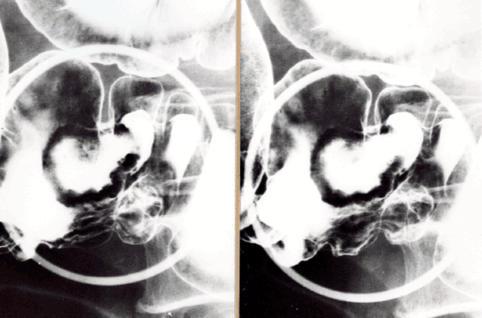

疾患(病理主体)の分類悪性上皮性腫瘍/腺癌

部位(臓器別)大腸/回盲部

検査方法X-P

腫瘍の肉眼分類2型(潰瘍限局型)/

病変の最大径(ミリ)30〜34